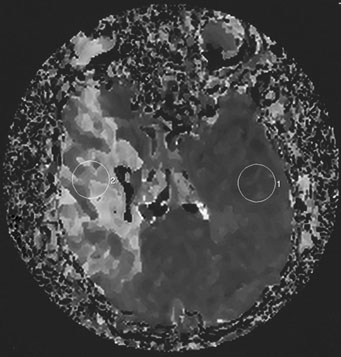

In the evaluation of extracranial large vessel disease, mainly carotid disease, ultrasound is the initial indicated study. It is commonly available, relatively inexpensive, and accurate. In addition, compared to other vascular imaging methods, it has the ability to directly image and characterize the plaque. Certain plaque characteristics may predict an increased risk of embolization. For example, the presence of an ulcer at the plaque surface may promote the formation of thrombus that can secondarily embolize, while a hypoechoic plaque, representing either intraplaque hemorrhage or a lipid-rich plaque, is associated with the potential for plaque destabilization.79,80 Carotid artery ultrasound has a sensitivity of 90% to 95% and specificity of 85% compared to catheter angiography.81 However, ultrasound may be unable to detect high-grade stenosis and mistakenly diagnose a carotid occlusion in 5% of cases. It is important to make this distinction as a patent vessel may be amenable to a revascularization procedure. Although power Doppler and echo-contrast agents may improve the odds of a correct diagnosis, for now it is standard practice to corroborate carotid occlusions with another imaging modality such as MRA, computed tomographic angiography (CTA), or conventional catheter angiography. MRA is an evolving technology comparable in accuracy to ultrasound, with the advantage of being able to image the distal carotid. In the past, there was a risk of overestimation of carotid stenosis by MRA, and beyond 70% stenosis, the absence of signal (flow gap) impeded adequate quantification of narrowing.82 Evolution in MRA technology and the use of contrast agents has improved the yield of this diagnostic method. Catheter angiography is the gold standard for carotid disease, but has inherent risks, with approximately 1% risk of stroke, although probably less in experienced centers. Figure 2 demonstrates the use of imaging technology in carotid disease.

Fig. 2. This 48-year-old diabetic man suddenly developed confusion and clumsiness of the right hand. On examination, he had inability to identify objects by touch and difficulty identifying the right from the left. A. Fluid attenuated inversion recovery (FLAIR) MRI shows a left parietal cortical infarct. Two potential embolic sources were noted: a left ventricular apical clot was seen on echocardiography from a presumed recent silent myocardial infarction, and ultrasound and subsequent angiography confirmed a significant left internal carotid stenosis. B: A 70% left internal carotid artery origin stenosis is shown on angiography. Monitoring both middle cerebral arteries with transcranial Doppler showed microembolic signals only over the left, suggesting that the carotid atherostenotic plaque was active or destabilized. C: An interruption (arrow) of the normal Doppler flow pattern of the middle cerebral artery is shown, representing a microembolic signal. The artery was stented rather than revascularized by endarterectomy because of the recent myocardial infarction. D: A patent revascularized carotid is revealed by ultrasound; note the struts of the stent.